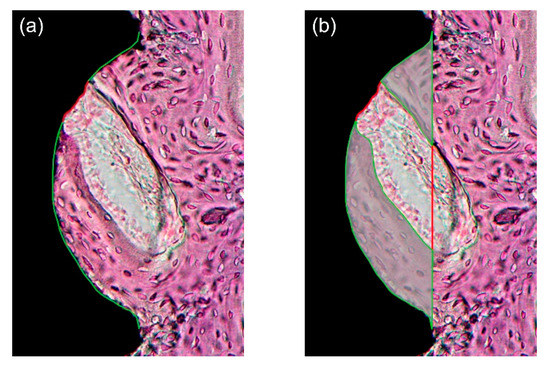

Representative photomicrographs are shown in Figure 6 and Figure 7; the results of the histomorphometric analysis are illustrated in Figure 8, Figure 9 and Figure 10. Apical migration of the epithelium and connective tissue was not observed in any of the samples. In the 2-week group, on the sides with bone grafting, a sparse amount of new bone in the vicinity of the implants was observed in the majority of the specimens, regardless of the method of surface modification used (Figure 7b,d). Therefore, the examiners were unable to perform histomorphometric measurements.

Figure 7.

Representative photomicrographs (40× magnification) of hematoxylin and eosin-stained histological sections of rabbit tibias at the implanted regions. (a) Group C-2, nongrafted side; (b) Group C-2, grafted side; (c) Group SU-2, nongrafted side; (d) Group SU-2, grafted side; (e) Group C-4, nongrafted side; (f) Group C-4, grafted side; (g) Group SU-4, nongrafted side; and (h) Group SU-4, grafted side. Note the sparse amount of new bone on the grafted side in 2-week groups. Scale bars: 500 μm.

In the nongrafted sides, bone neoformation was found at the bone/implant interface in cortical bone (Figure 7a,c). The mean BIC values of group U-2, S-2, and SU-2 were 85.2%, 80.9%, and 83.2% respectively. These values were significantly higher (approximately 20%) than the BIC value (59.3%) of group C-2 (p < 0.05) (Figure 8a). There was no statistically significant difference in the BIC values among the experimental groups (p > 0.05). The BA values did not differ significantly among the four groups (p > 0.05) (Figure 8b).

In the sides contacting the innate bone, the amount of newly formed bone in direct contact with the implant surface was more prominent in comparison with that in the 2-week group (Figure 7e,g). The mean BIC values of group U-4, S-4, and SU-4 were 91.2%, 85.2%, and 84.6%, respectively. Similar to the 2-week group, the BIC values of group U-4, S-4, and SU-4 were approximately 20% higher than the BIC value (66.2%) of group C-4 (p < 0.05) (Figure 8c). There was no statistically significant difference in the BIC values among the experimental groups (p > 0.05). The BA values did not differ significantly among the four groups (p > 0.05) (Figure 8d). The overall numerical tendency was analogous to that of the 2-week group.

On the sides with bone grafts, newly formed bone was observed at the bone/implant interface and around the biomaterial (Figure 7f,h). The bone graft materials were not degraded during this period and were discernible from the newly formed bone. Both the BIC and BA values of group U-4, S-4, and SU-4 were significantly larger (about 20%) than those of group C-4 (p < 0.05) (Figure 8e,f). There was no significant difference in either parameter among group U-4, S-4, and SU-4 (p > 0.05). When the nongrafted and grafted sides in the 4-week group were compared, there was no significant difference between them in terms of BIC and BA (p > 0.05), regardless of the surface treatment methods used (Figure 9).